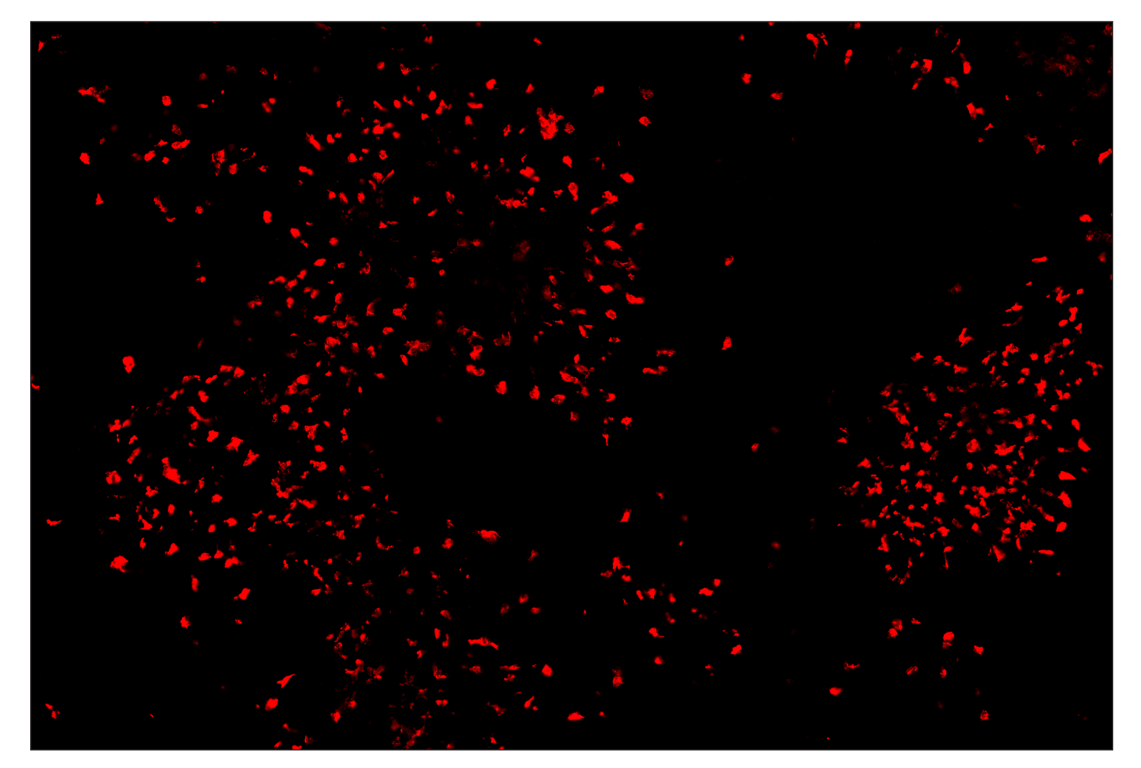

SignalStar™ multiplex immunohistochemical analysis of paraffin-embedded GL261 syngeneic tumor using Arginase-1 (D4E3M) & CO-0075-594 SignalStar™ Oligo-Antibody Pair #66757 (red) and F4/80 (D2S9R) & CO-0042-750 SignalStar™ Oligo-Antibody Pair #51924 (cyan). All fluorophores have been assigned a pseudocolor, as indicated. Staining was performed on the BOND RX autostainer by Leica Biosystems.

Immunohistochemistry Image 6: Arginase-1 (D4E3M) & CO-0075-750 SignalStar<sup>™</sup> Oligo-Antibody Pair